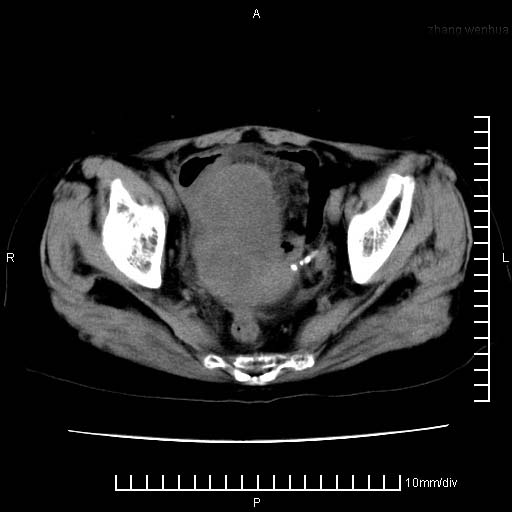

下腹疼痛2月,加重并呕吐2天,下腹压痛,反跳痛。白细胞1万2.

下腹至盆腔较大包块,与邻近肠管关系密切,下腹疼痛2月,加重并呕吐2天,下腹压痛,反跳痛。白细胞1万2.

由于没有做肠道准备很难分清是哪根肠管,但看位置考虑为升结肠回盲部的问题,我首先考虑化脓性阑尾炎,不除外结肠癌合并感染化脓。建议做增强进一步明确。

补充:道格拉斯腔内有积液,且密度较高,显然提示有感染。